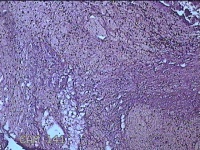

子宫腔内组织

性别

女

年龄

39岁

临床诊断

早期人工流产

一般病史

停经36天。

标本名称

大体所见

灰白暗红色不规则碎组织3x2.5x1.3cm一堆,未发现明显的绒毛样组织。

不具诊断价值。

在切片质量方面还需要加把劲。